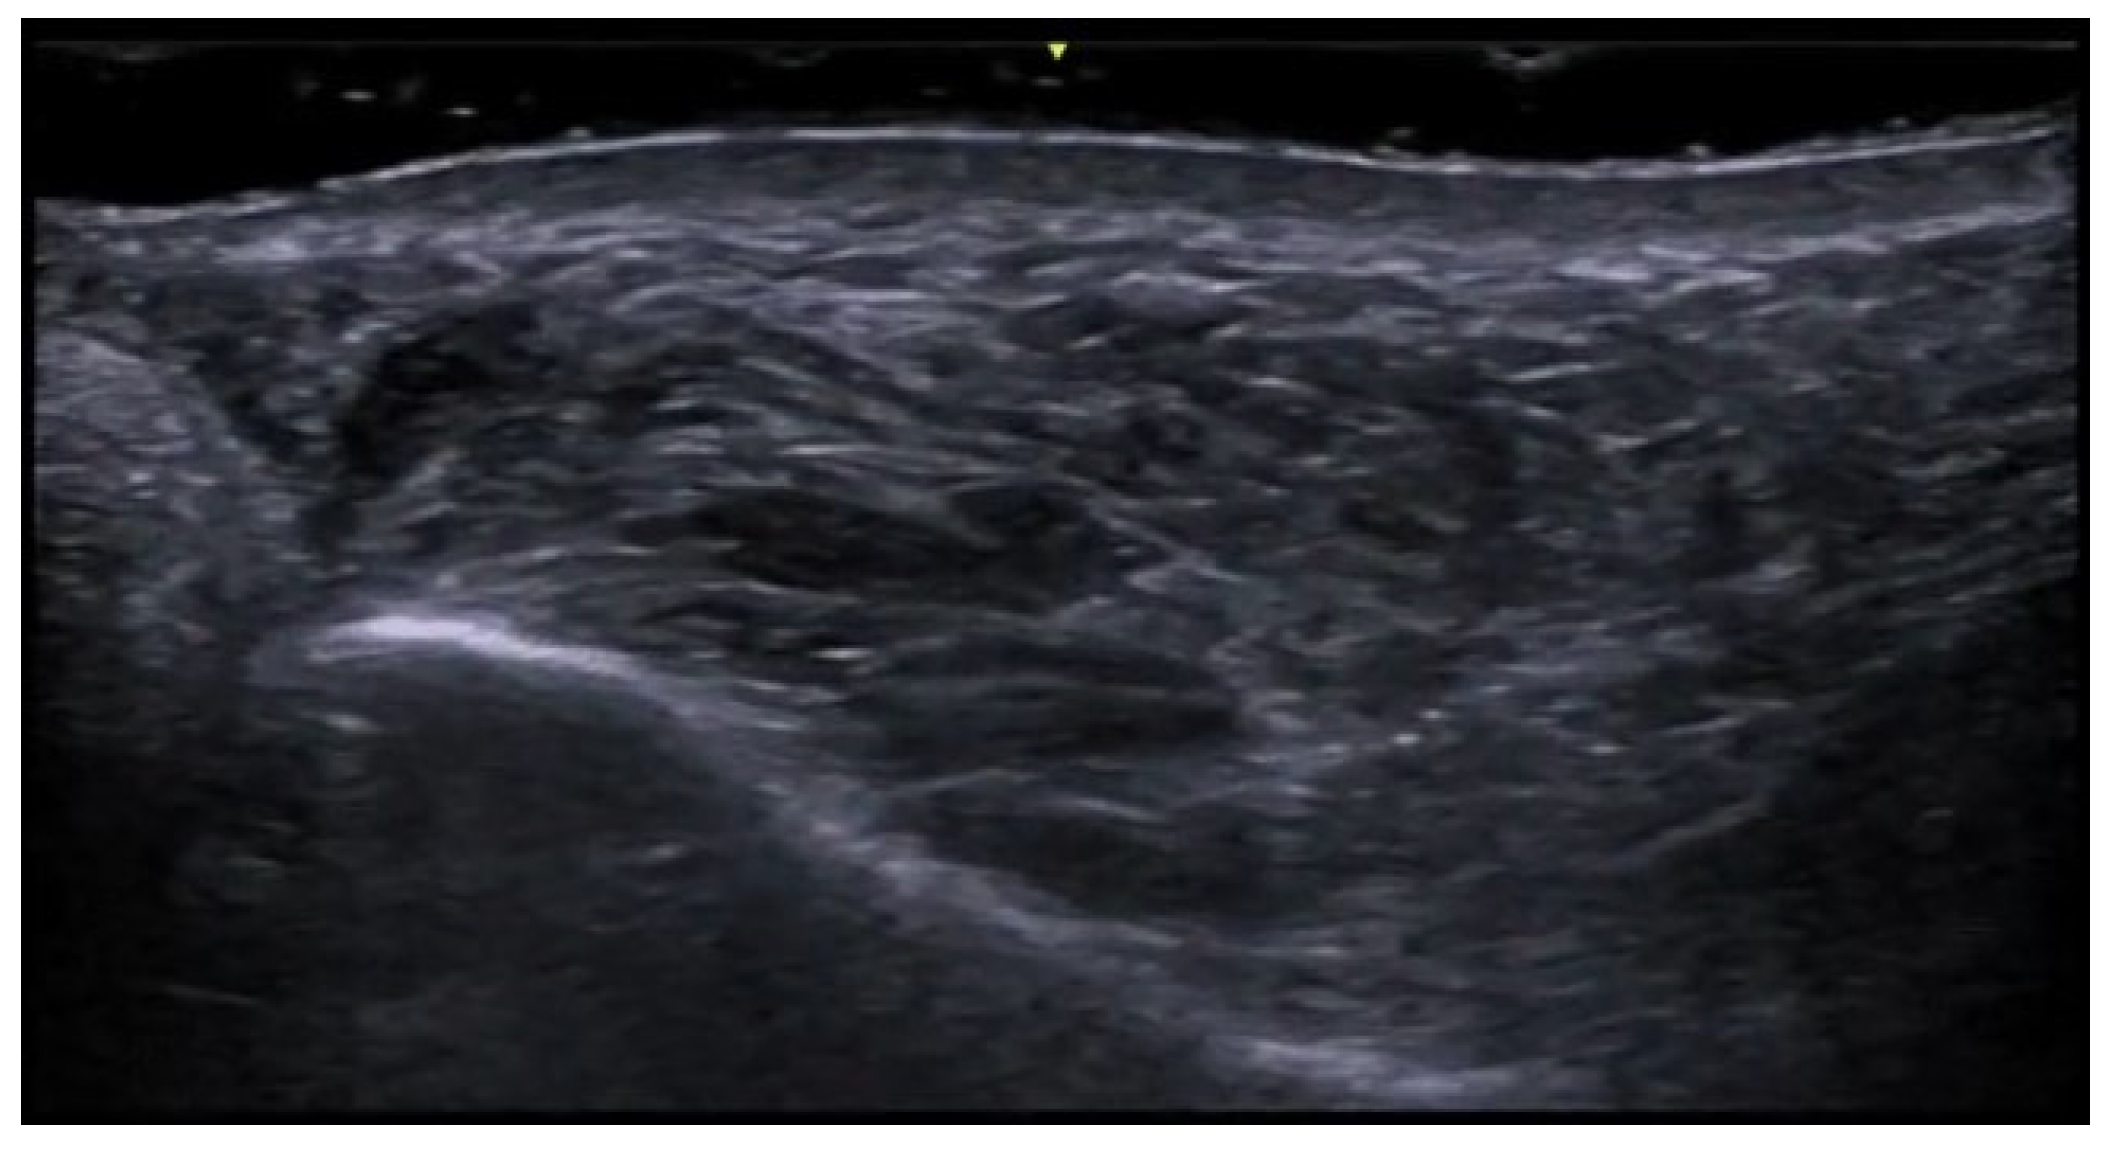

5. Specific Cutaneous Structure and Sites of Skin Disorders